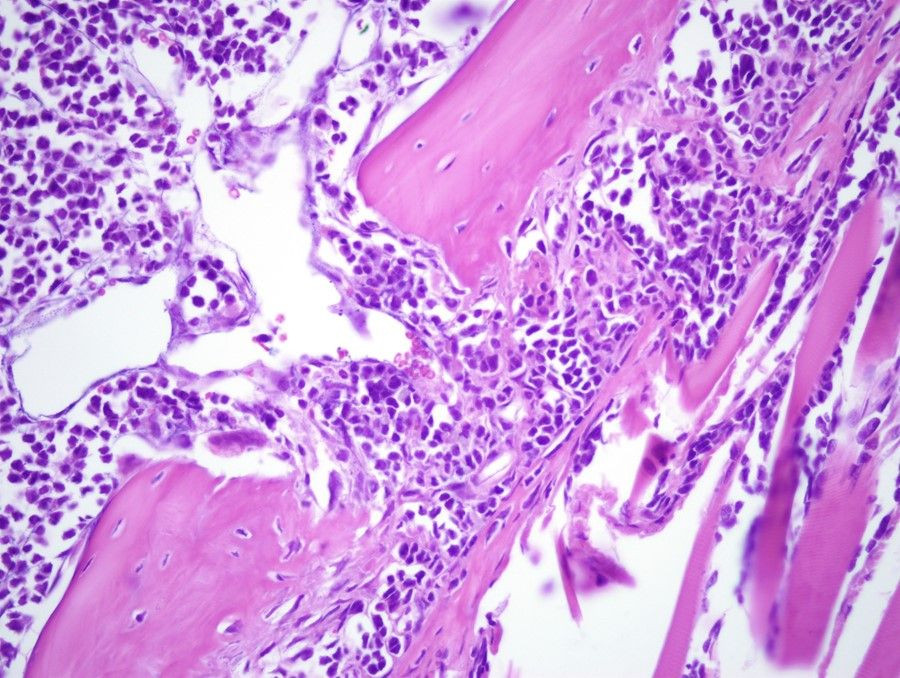

El mieloma múltiple es un tipo de cáncer de la sangre en el que las células inmunitarias crecen de forma descontrolada en la médula ósea. Es muy difícil de tratar y todavía se considera incurable, por lo que es urgente identificar nuevas dianas terapéuticas en las células cancerosas.

El grupo de investigación del nuevo estudio ha demostrado anteriormente que las células de mieloma múltiple cultivadas tenían un crecimiento reducido e incluso se destruían si se trataban con una sustancia que inhibía la proteína EZH2. Ahora encontraron que la inhibición de EZH2 también redujo el crecimiento del cáncer en un modelo de ratón con mieloma múltiple.

"Tratamos ratones con un tipo de cáncer que corresponde al mieloma múltiple humano con una sustancia que inhibe EZH2 y descubrimos varios signos de que los ratones tratados tenían un crecimiento del cáncer más lento que los ratones no tratados --explica Helena Jernberg Wiklund, profesora del Departamento de Inmunología, Genética y Patología y directora del estudio--. Esto proporcionó más evidencia del potencial de EZH2 como un objetivo de la intervención clínica".

Los resultados del modelo de ratón animaron a los investigadores a investigar más a fondo qué es lo que hace que las células sean sensibles a la inhibición de EZH2. Las células de mieloma múltiple humano son más heterogéneas que las células modelo de ratón y encontraron que algunos tipos de células de mieloma múltiple cultivadas en humanos eran sensibles mientras que otras eran resistentes.